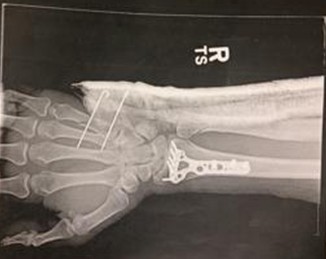

Bike Crash injury Bike Crash injury admin2025-04-17T14:33:48+00:00April 17th, 2025| Share This Story, Choose Your Platform! FacebookXRedditLinkedInWhatsAppTumblrPinterestVkEmail